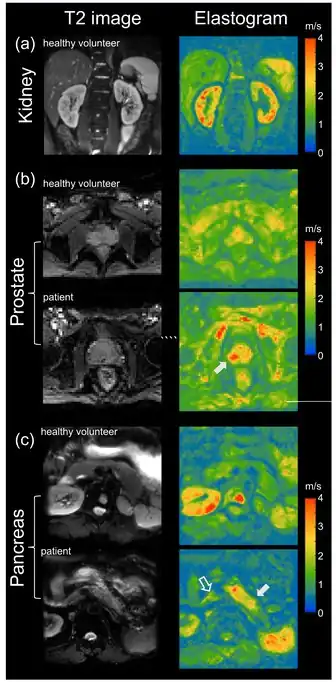

MRE has also been applied to investigate the biomechanical properties of the kidney. The feasibility of clinical renal MRE was first reported in 2011 for healthy volunteers [42] and in 2012 for renal transplant patients.[43] Renal MRE is more challenging than MRE of larger organs such as the brain or liver due to fine mechanical features in the renal cortex and medulla as well as the acoustically shielded position of the kidneys within the abdominal cavity. To overcome these challenges, researchers have been looking at different passive drivers and imaging techniques to best deliver shear waves to the kidneys.[44][45][46][47][48] Studies investigating renal diseases such as renal allograft dysfunction,[49][50][51][52] lupus nephritis,[53] immunoglobulin A nephropathy (IgAN),[54] diabetic nephrology,[55] renal tumors[56] and chronic kidney disease[57] demonstrate that kidney stiffness is sensitive to kidney function[58][59] and renal perfusion.[58][60]

Prostate

The prostate can also be examined by MRE, in particular for the detection and diagnosis of prostate cancer.[61] To ensure good shear wave penetration in the prostate gland, different actuator systems were designed and evaluated.[62][63] Preliminary results in patients with prostate cancer showed that changes in stiffness allowed differentiation of cancerous tissue from normal tissue.[64] Magnetic Resonance Elastography has been successfully used in patients with prostate cancer showing high specificity and sensitivity in differentiating prostate cancer from benign prostatic diseases [65][66] (see figure on right (b)). Even higher specificity of 95% for prostate cancer was achieved when Magnetic Resonance Elastography was combined with systematic image interpretation using PI-RADS (version 2.1).[66][67]

Pancreas

The pancreas is one of the softest tissues in the abdomen. Given that pancreatic diseases including pancreatitis and pancreatic cancer significantly increase stiffness, MRE is a promising tool for diagnosing benign and malignant conditions of the pancreas. Abnormally high pancreatic stiffness was detected by MRE in patients with both acute and chronic pancreatitis.[68] Pancreatic stiffness was also used to distinguish pancreatic malignancy from benign masses [69] and to predict the occurrence of pancreatic fistula after pancreaticoenteric anastomosis.[70] Quantification of the volume of pancreatic tumors based on tomoelastographic measurement of stiffness was found to be excellently correlated with tumor volumes estimated by contrast-enhanced computed tomography.[71] In patients with pancreatic ductal adenocarcinoma stiffness was found to be elevated in the tumor as well as in pancreatic parenchyma distal to the tumor, suggesting heterogeneous pancreatic involvement [72] (figure on right (c)).